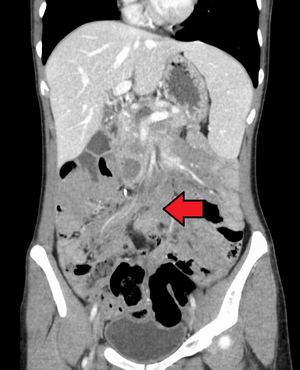

ورم رباطي كما هو موضح في الاشعة المقطعية